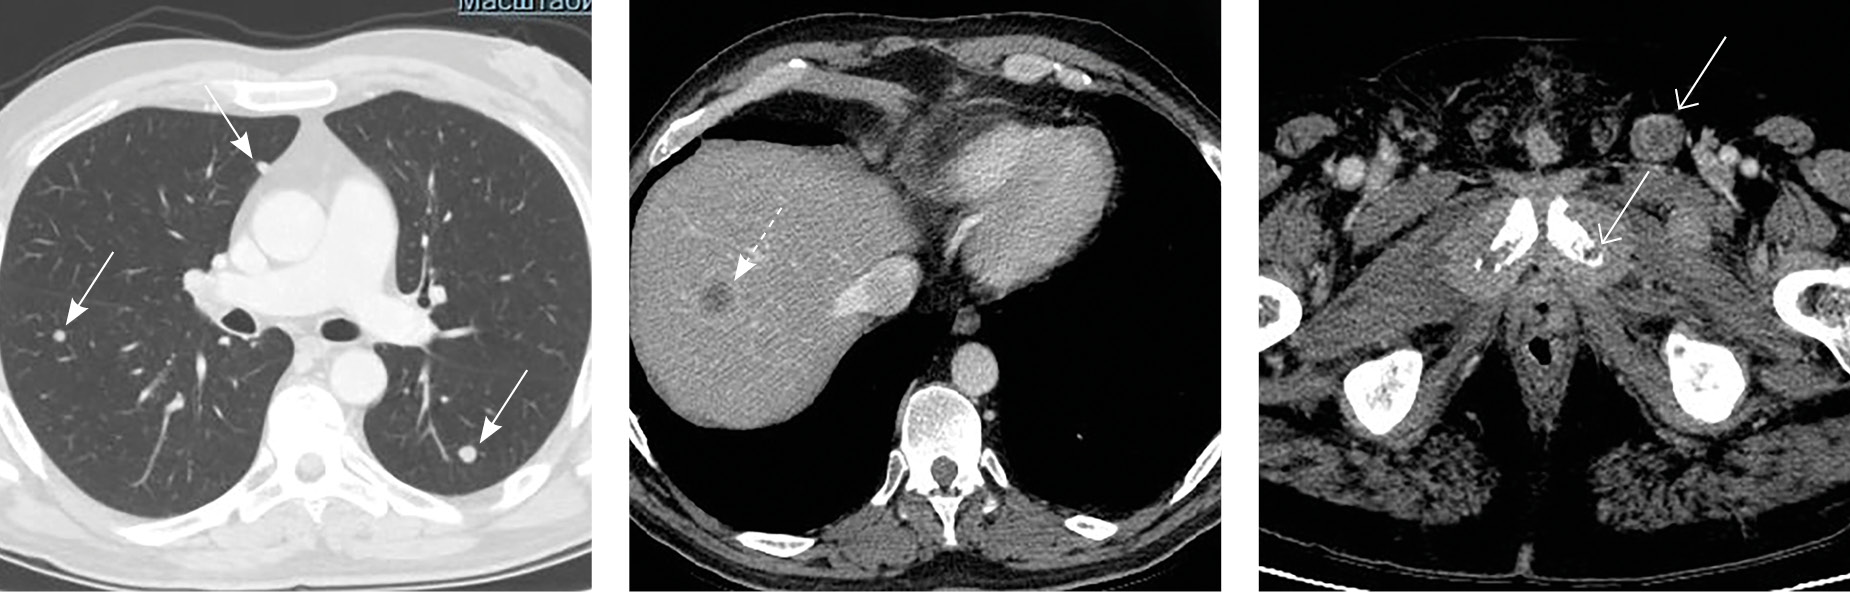

Через 10 месяцев после ЦЭ (18.05.2020) при МРТ малого таза (рис. 2) по ходу наружных подвздошных сосудов слева обнаружено мягкотканное образование размером до 92 мм, накапливающее контрастный препарат, с деструкцией левых отделов крестца (до 52 мм) в месте его прилежания к вышеуказанному образованию. С диагнозом регионарного рецидива в зоне подвздошных лимфоузлов с 06.07.2020 по 21.08.2020 пациенту проведена дистанционная лучевая терапия только на область подвздошных лимфоузлов слева до суммарной очаговой дозы 57,5 Гр с одновременной химиотерапией цисплатином.

Рис. 2. Магнитно-резонансная томограмма малого таза, после радикальной цистпростатэктомии. Прогрессирование заболевания: множественные метастазы в подвздошные лимфоузлы (сплошные стрелки), пресакральную клетчатку и боковые массы крестца слева (пунктирная стрелка), а также вторичное поражение губчатой части мочеиспускательного канала на значительном протяжении с инвазией губчатого и пещеристых тел (открытые стрелки)

23.10.2020 (через 15 месяцев после ЦЭ) в связи с жалобами на уретроррагию и приапизм, который сопровождался выраженным болевым синдромом, выполнена МРТ малого таза. Диагностирован УР размером 103 × 38 мм в границах проксимального отдела полового члена (область губчатого сегмента уретры) с инвазией кавернозных тел (см. рис. 2). 03.12.2020 выполнена ампутация полового члена. В послеоперационном периоде болевой синдром полностью регрессировал.